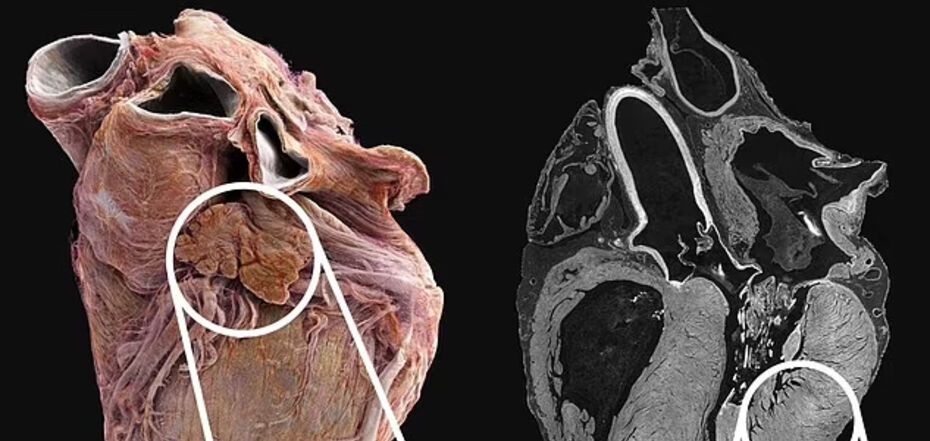

The video compares two whole organs from deceased adult donors. The healthy heart is from a 63-year-old man. The diseased one is from an 87-year-old woman with a history of coronary heart disease, when the organ is weakened due to decreased blood flow. The difference is obvious: a healthy heart has a well-defined shape, while a sick heart is rounder, with dried vessels and muscle fibers.

A team of scientists used an X-ray technique called hierarchical phase-contrast tomography (HiP-CT) to image the heart at a scale of 20 micrometers.